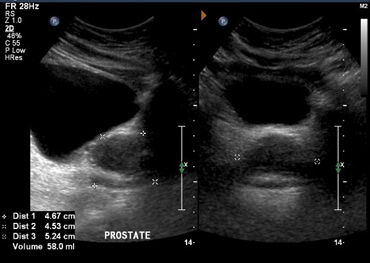

Transabdominal

In a transabdominal examination, the bladder is situated above the prostate

Sagittal

Transverse